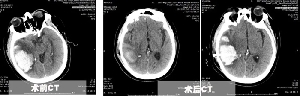

精準微創手術,重癥腦出血患者快速康復

近日,患者王先生將一面錦旗親手送給神經外一科李永濤主任。患者王先生,62歲,體重200余斤,糖尿病、冠心病、腦梗塞病史3年余,長期口服二甲雙胍、阿司匹林、瑞舒伐他汀等藥物,病情控制一般。7月8日,患者突發頭痛頭暈,出現一側肢體偏癱、意識障礙,急診行顱腦CT提示枕頂葉大面積腦出血,血腫量超過50ml,有手術指征。據